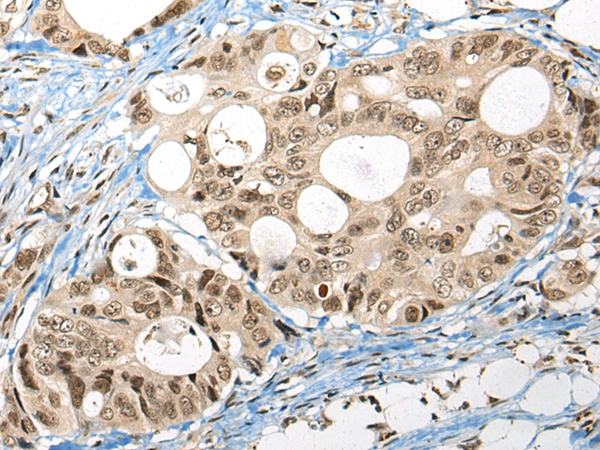

The image on the left is immunohistochemistry of paraffin-embedded Human liver cancer tissue using 46565(FUT4 Antibody) at dilution 1/40, on the right is treated with synthetic peptide. (Original magnification: x200)

The image on the left is immunohistochemistry of paraffin-embedded Human colorectal cancer tissue using 46565(FUT4 Antibody) at dilution 1/40, on the right is treated with synthetic peptide. (Original magnification: x200)